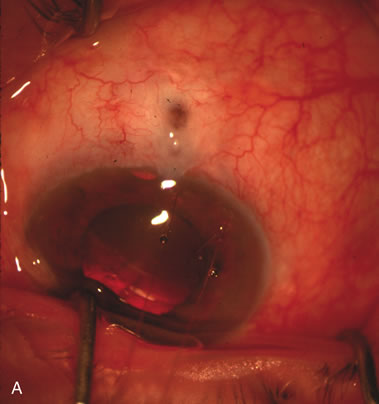

CATARACT EXTRACTION ALONE REDUCES IOP IN MOST EYES WITH ANGLE-CLOSURE GLAUCOMA

Uncomplicated cataract extraction substantially reduces IOP, along with the number of postoperative glaucoma medications in eyes with angle-closure glaucoma.146,147 When preoperative gonioscopy reveals PAS, along with adjacent areas of appositional closure, lens extraction alone in select cases may be a reasonable alternative to filtration surgery.148,149 Phacomorphic angle-closure disease due to enlargement of the lens with progressive angle crowding is eliminated following lens extraction. The width and depth of the anterior chamber angle in eyes with angle-closure glaucoma increases significantly after cataract extraction with IOL implantation and becomes similar to open-angle glaucoma and normal eyes.150,151 (Fig. 5). Combining phacoemulsification, IOL implantation, and limited goniosynechialysis is effective in the treatment of cataract and chronic angle-closure glaucoma.152 Phacoemulsification with implantation of a foldable IOL is more effective in reducing IOP and improving visual acuity than surgical peripheral iridectomy in eyes with acute angle-closure glaucoma.153

Fig. 5. Anterior chamber angle changes associated with lens extraction and PCIOL This 65-year-old Vietnamese woman has a long-standing history of chronic angle-closure glaucoma treated with laser peripheral iridectomy. The optic nerve demonstrated mild glaucomatous damage and IOP was moderately controlled on two antiglaucoma medications. The cataract was removed through temporal clear corneal phacoemulsification with foldable acrylic IOL. A. Symptomatic cataract in narrow-angle glaucoma eye with patent iridectomy. B. Intraoperative goniophotograph showing crowding of angle with increasing narrowness due to phacomorphic component. C. Intraoperative photograph showing temporal clear corneal approach with IOL in the capsular bag. D. Intraoperative goniophotograph demonstrating deepening of chamber angle following lens extraction. Proposed theories for IOP reduction following lens extraction with complete wound closure: